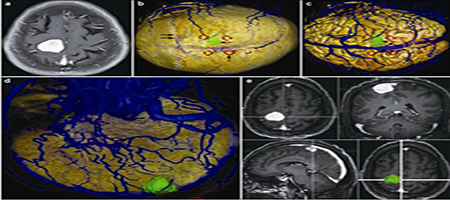

8. Application of multimodal image fusion technology in brain tumor surgical procedure

Jiefei Li, Yuqi Zhang, Le He, Huancong Zuo

临床转化神经科学    2016, 2 (4): 215-226.   DOI: 10.18679/CN11-6030/R.2016.035

摘要619)      PDF (5118KB)(529)

Objective: To construct brain tumors and their surrounding anatomical structures through the method of registration, fusion and, three-dimensional (3D) reconstruction based on multimodal image data and to provide the visual information of tumor, skull, brain, and vessels for preoperative evaluation, surgical planning, and function protection.

Methods: The image data of computed tomography (CT) and magnetic resonance imaging (MRI) were collected from fifteen patients with confirmed brain tumors. We reconstructed brain tumors and their surrounding anatomical structures using NeuroTech software.

Results: The whole 3D structures including tumor, brain surface, skull, and vessels were successfully reconstructed based on the CT and MRI images. Reconstruction image clearly shows the tumor size, location, shape, and the anatomical relationship of tumor and surrounding structures. We can hide any reconstructed images such as skull, brain tissue, blood vessles, or tumors. We also can adjust the color of reconstructed images and rotate images to observe the structures from any direction. Reconstruction of brain and skull can be semi transparent to display the deep structure; reconstruction of the structures can be axial, coronal, and sagittal cutting to show relationship among tumor and surrounding structures. The reconstructed 3D structures clearly depicted the tumor features, such as size, location, and shape, and provided visual information of the spatial relationship among its surrounding structures.

Conclusions: The method of registration, fusion, and 3D reconstruction based on multimodal images to provide the visual information is feasible and practical. The reconstructed 3D structures are useful for preoperative assessment, incision design, the choice of surgical approach, tumor resection, and functional protection.

图表 | 参考文献 | 相关文章 | 多维度评价